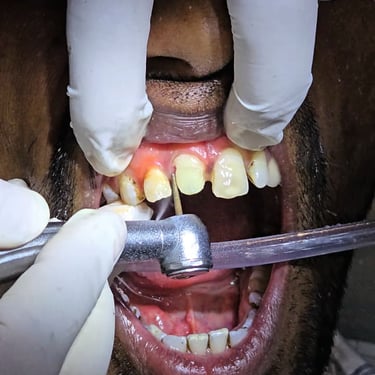

Step 3: Fiber Post Placement

After successful RCT, a fiber post was placed inside the canal. The fiber post strengthens the tooth internally and provides a solid foundation for the core and crown. Compared to metal posts, fiber posts are aesthetic, biocompatible, and long-lasting.

Step 4: Core Build-Up

A core build-up was done over the fiber post to rebuild the lost tooth structure. This step ensures proper retention and stability for the cap (crown) that will be placed later.